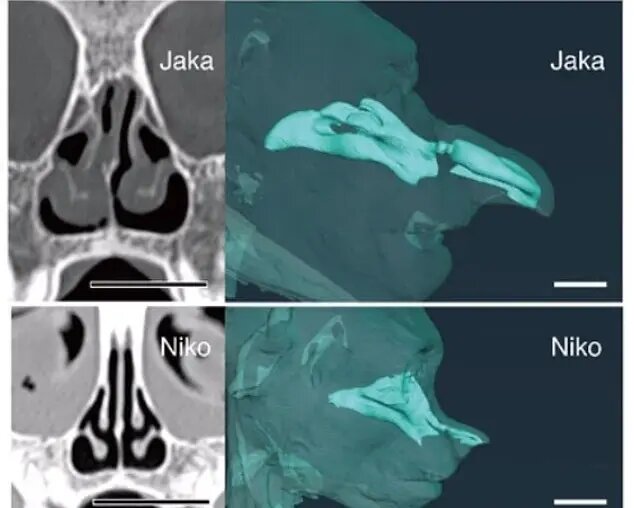

محققان دانشگاه اوزاکا، سیتیاسکنهایی را روی نمونههای گرفته شده از میمونهای بینیدراز انجام دادند که به آنها امکان داد مدلهای دیجیتالی سهبعدی دقیقی از مجاری بینی این میمونها بسازند.

به عنوان بخشی از مطالعه، آنها سیتیاسکن یک میمون بالغ نر بینیدراز به نام جاکا را با یک میمون نابالغ به نام نیکو مقایسه کردند. بینی جاکا به طور قابل توجهی بزرگتر بود و آزمایشها نشان داد که او صداهایی با فرکانس پایینتر تولید میکرد.